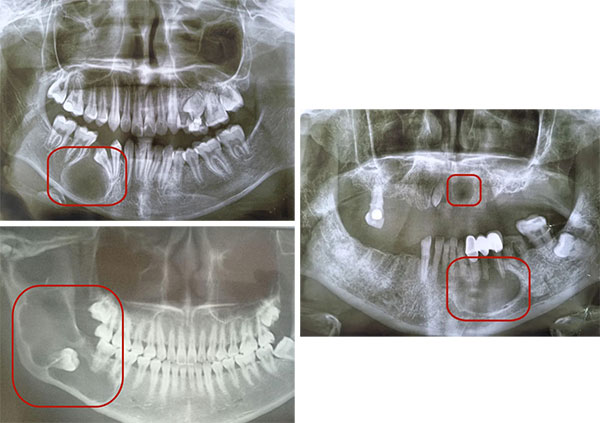

作为口腔颌面外科医生,发现患有颌骨囊肿的患者有递增的趋势,我曾在手术中取出过拳头大小的颌骨囊肿,也遇到过因拖延治疗导致半侧下颌骨被“掏空”的病例,还有患者拿着CT报告惊慌失措地问:“医生,我骨头里怎么长了个‘水泡’,不痛不痒需要治吗?”今天,我就来揭开这个“沉默杀手”的真面目。

核心特征:早期生长缓慢、症状隐蔽,多数患者因颌骨膨隆、牙齿松动或拍片偶然发现。

X线片:显示圆形/椭圆形低密度阴影,边缘光滑;

CBCT(三维CT): 精确定位囊肿范围与重要结构(如下颌神经管)的关系。